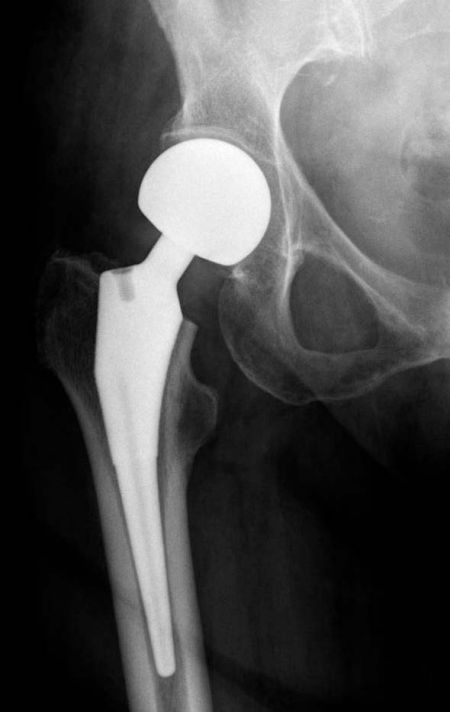

Cementna ili bescementna hemiartroplastika za intrakapsularni prijelom kuka

Provedeno je multicentrično, randomizirano, kontrolirano ispitivanje u kojem se uspoređivalo cementnu s bescementnom hemiartroplastikom u bolesnika u dobi od 60 godina ili starijih s intrakapsularnim prijelomom kuka. Primarni ishod bila je kvaliteta života povezana sa zdravljem mjerena korištenjem upitnika EuroQol Group 5-Dimension (EQ-5D) četiri mjeseca nakon randomizacije, s višim rezultatima koji ukazuju na bolju kvalitetu života.

Ukupno 610 pacijenata bilo je podvrgnuto cementnoj hemiartroplastici, a 615 modernoj bescementnoj hemiartroplastici. Nakon četiri mjeseca, podaci o praćenju bili su dostupni za 71,6% bolesnika. Razlika između skupina nakon jednog mjeseca bila je slična onoj nakon četiri mjeseca, ali je razlika nakon 12 mjeseci bila manja od one nakon četiri mjeseca. Smrtnost nakon 12 mjeseci bila je 23,9% u cementnoj skupini i 27,8% u bescementnoj. Periprostetski prijelomi dogodili su se u 0,5% u cementnoj i 2,1% bolesnika u bescementnoj skupini. Učestalost ostalih komplikacija bila je slična u dvije skupine.

Među pacijentima starijim od 60 godina s intrakapsularnim prijelomom kuka, cementna hemiartroplastika rezultirala je značajno boljom kvalitetom života i manjim rizikom od periprostetskih prijeloma od bescementne hemiartroplastike.